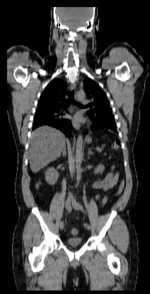

this is the fixed CT image. All images are aligned into this space this is the fixed PET image. All images are aligned into this space lleft this is the moving image. The transform is calculated by matching this to the reference image this is the moving image. The transform is calculated by matching this to the reference image

fixed image/target fixed image/target moving image moving image

• reference/fixed : baseline CT: 0.97 x 0.97 x 3.27 mm , 512 x 512 x 267; PET: 4.7 x 4.7 x 3.3 mm , 128 x 128 x 267